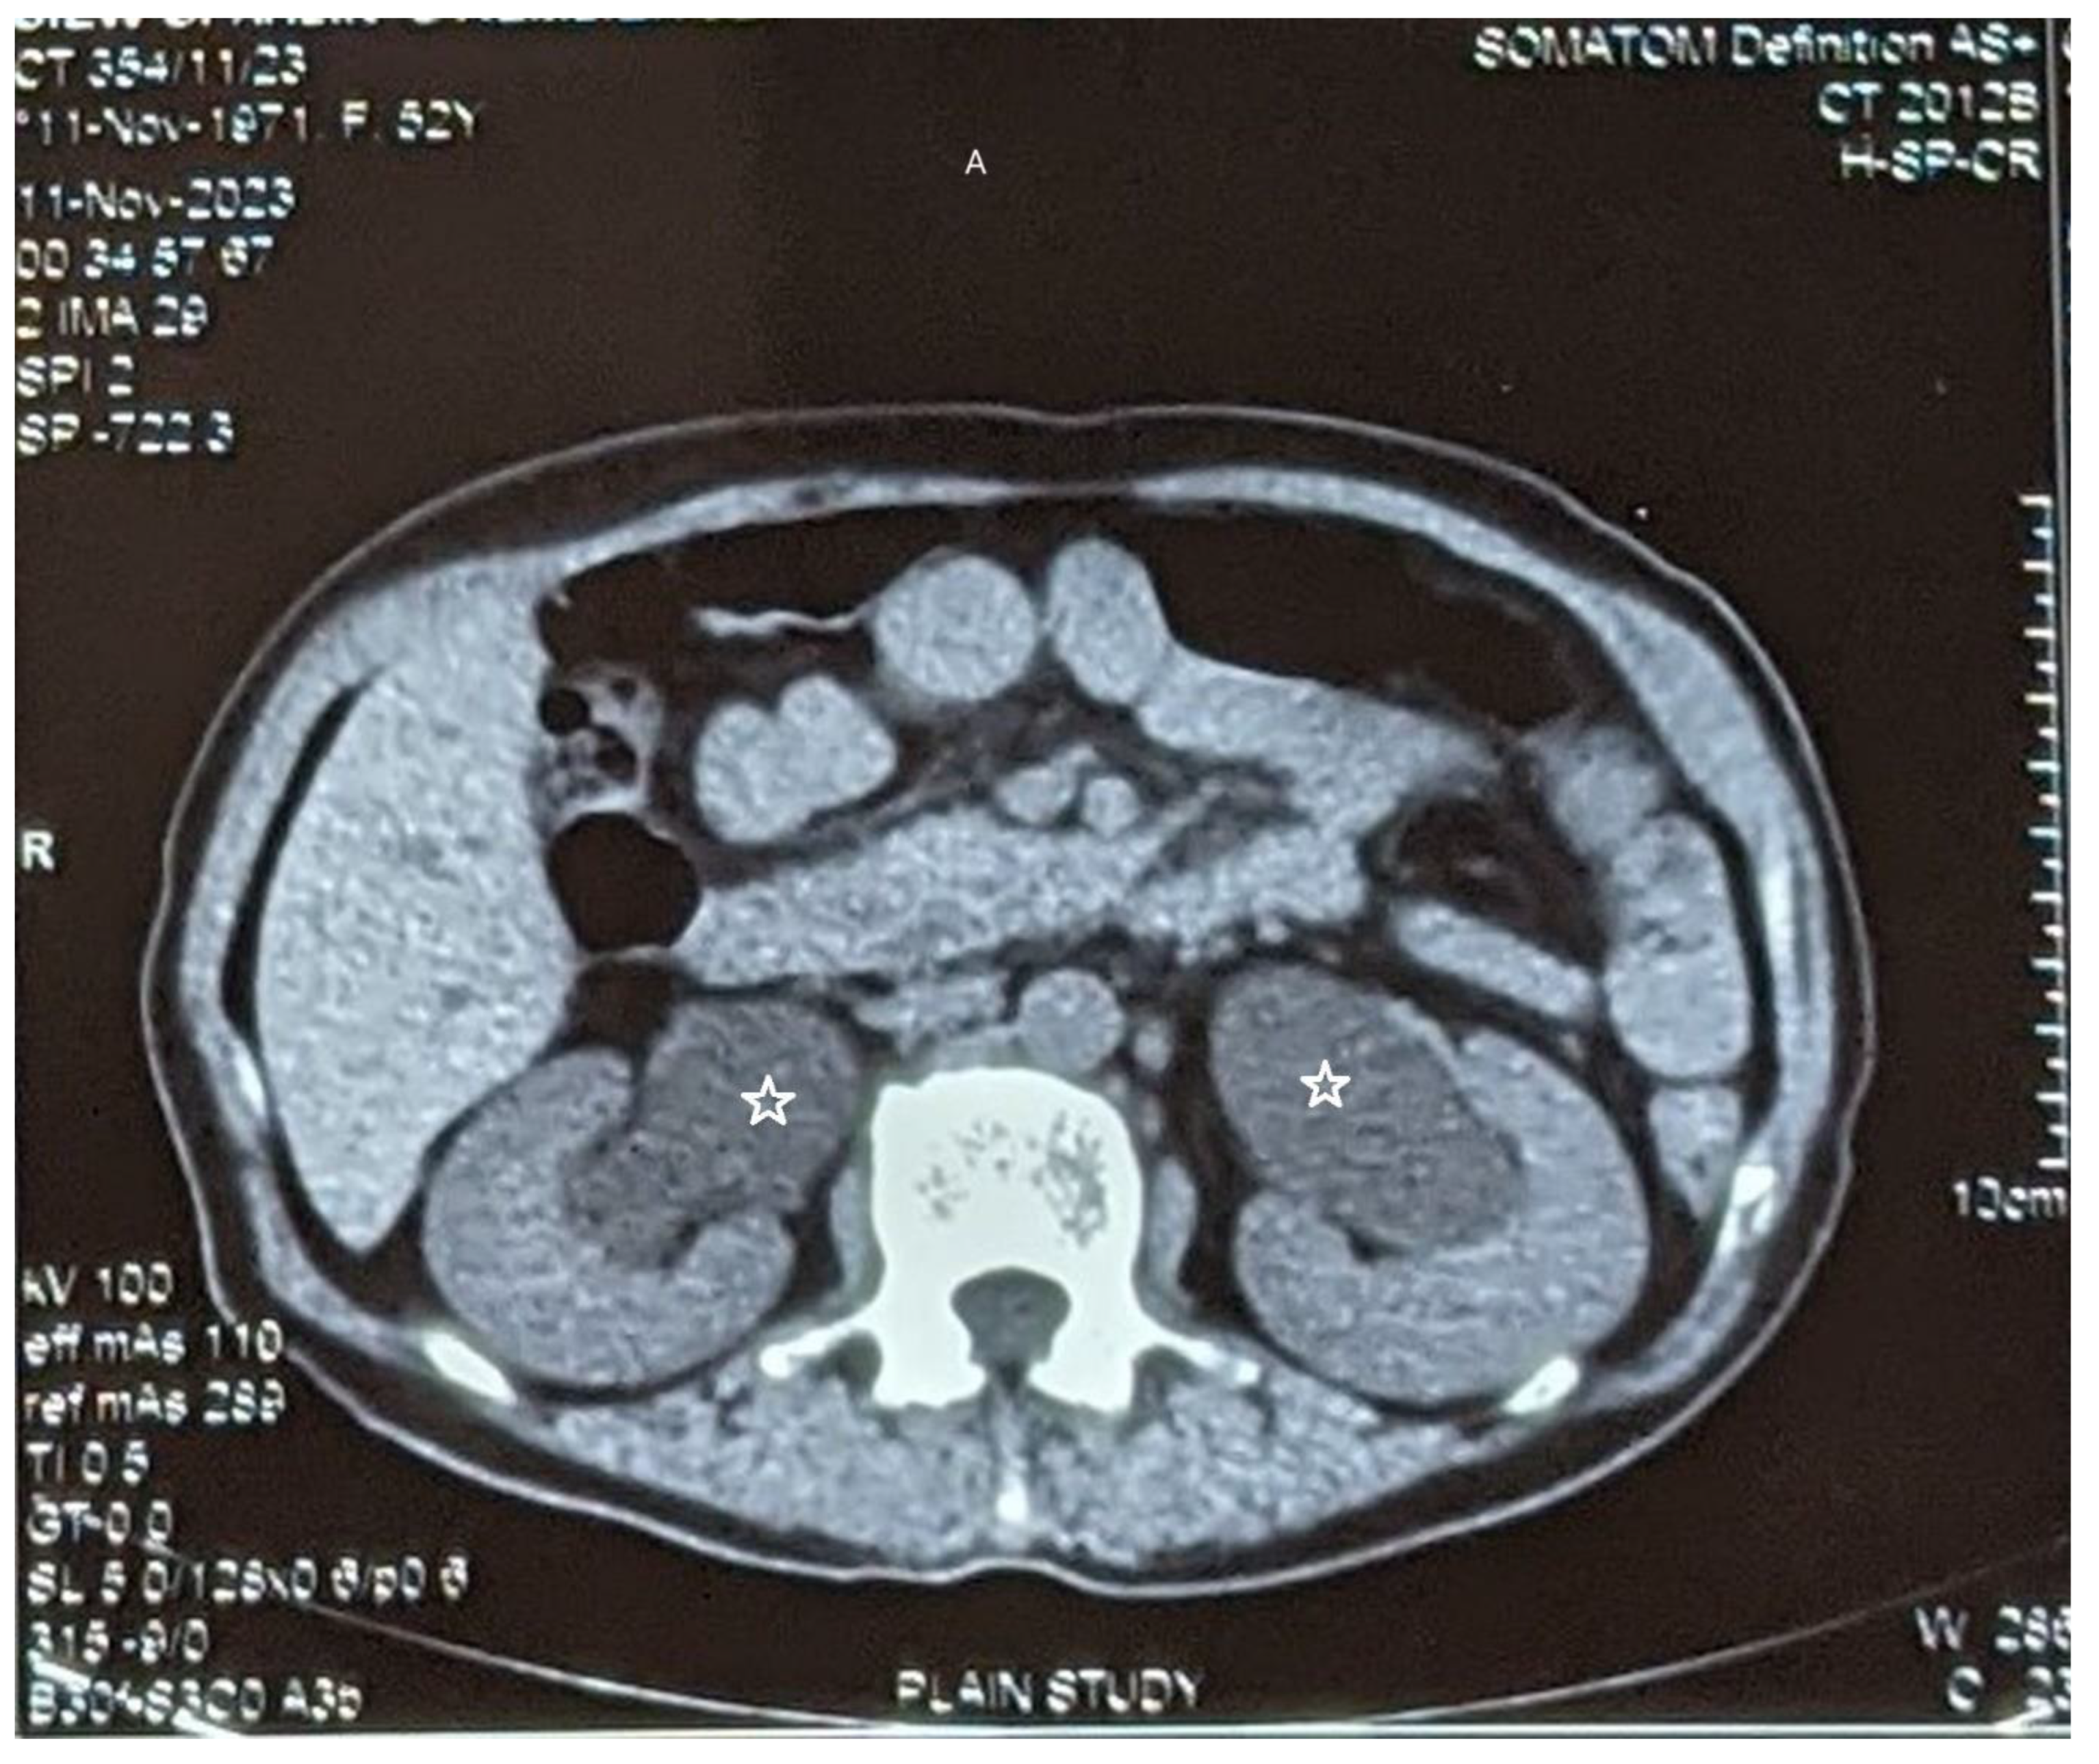

CT scan (non-contrast) detected moderate bilateral hydronephrosis (Figure 1 A), intraluminal gas in urinary bladder with thickened walls indicative of emphysematous cystitis (Figure 1 B). At cystoscopy, a whitish mass filling up the urinary bladder was found. While the mass was being resected with resectoscope (Figure 1C), the mass extruded in toto into the vagina through a vesico-vaginal fistula (Figure 1 D). The histopathological report demonstrated predominantly necrotic material, fungal organism in the form of spores and hyphae. PAS and GMS stain were positive for fungal organism. Ultrasonography repeated after 14 days of Fluconazole showed resolution of hydronephrosis. Patient was scheduled for repair of the fistula but she did not report for the repair.

Figure 1. A: CT scan (non-contrast) showing bilateral moderate hydronephrosis (star).